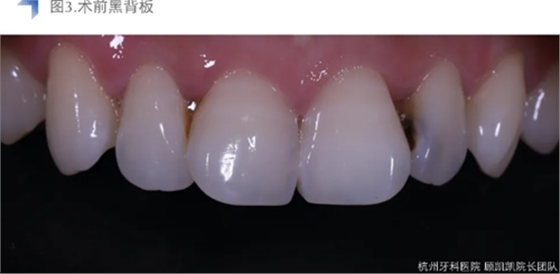

患者因左上前牙逐渐发黑,进食时冷热不适就诊,未有明显自发性疼痛。

接诊后口内检查12近中邻面较大面积龋齿,探不适,叩无不适,冷热测试同时对照牙及临牙,BOP+,扪诊(-),未有异常松动度。术前CBCT检查如下图,未见明显根尖周透射影。

考虑到术前口内检查及影像学检查提示龋损较近髓,与患者沟通可能设计牙髓治疗。考虑到美学及长期稳定考量,与患者沟通直接树脂充填与间接瓷贴面修复两种修复方式,患者考虑后决定采用间接椅旁瓷贴面修复。